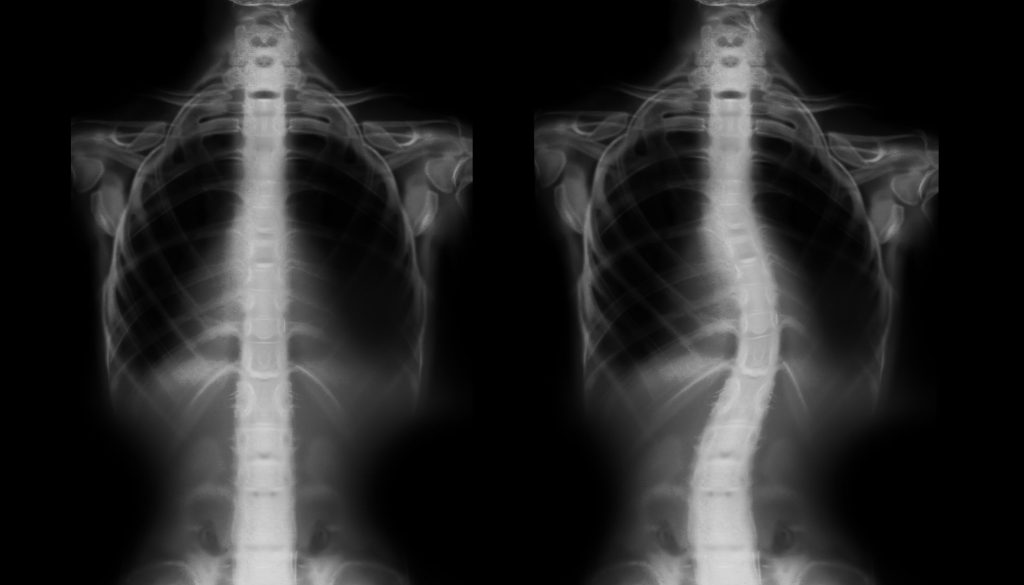

الاعوجاج الخلقي للعمود الفقري هو اضطراب هيكلي ينشأ نتيجة تشوهات خلقية في الفقرات منذ الولادة. يتضمن الاعوجاج الخلقي أنواعًا عديدة مثل “الجنف”، ويسبب تباينًا في انحناء العمود الفقري، مما قد يؤدي إلى مشاكل وظيفية وصحية لاحقة.

– **التصوير بالأشعة**: مثل الأشعة السينية، لإعطاء صورة واضحة عن شكل العمود الفقري.